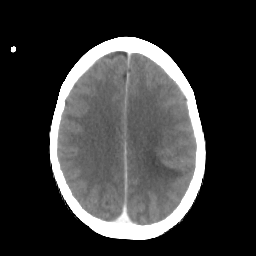

Metastatic bronchogenic carcinoma: Roentgen-ray CT -- Slice #15

[Home][Help][Clinical] Slice 15